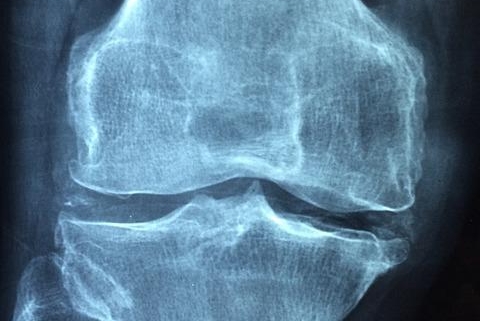

Osteoarthritis: This is the most common form of arthritis, caused by the breakdown of cartilage, the protective cushion between bones. This breakdown leads to bone rubbing against bone, causing pain, stiffness, and reduced range of motion. Risk factors include age, genetics, obesity, and previous joint injuries.